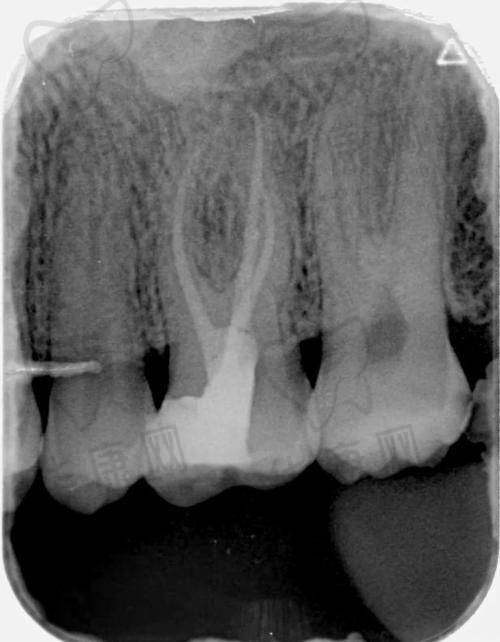

在沈阳地区,单颗牙齿的根管治疗费用通常在800 - 3000元之间。前牙治疗相对简单,费用一般在800 - 1500元,而后牙因根管结构复杂,费用较高,在1500 - 3000元。若需显微镜辅助或复杂修复,费用还会进一步增加。然而,沈阳牙元素口腔前牙单颗根管治疗361元起,这一价格远远低于市场平均水平。

根管治疗后,牙齿比较脆弱,需要进行适当的修复。沈阳牙元素口腔会根据患者牙齿的缺损情况,提供合理的修复建议。

对于轻度缺损的前牙,建议树脂补牙,费用在200 - 500元;中度缺损的前牙或后牙,建议嵌体修复,费用在1500 - 3500元;重度缺损的后牙或功能牙,建议全冠修复,费用在2000 - 5000元。同时,医院会提醒患者治疗后避免用患牙咀嚼硬物,并定期复查,确保治疗成效的长期稳定。